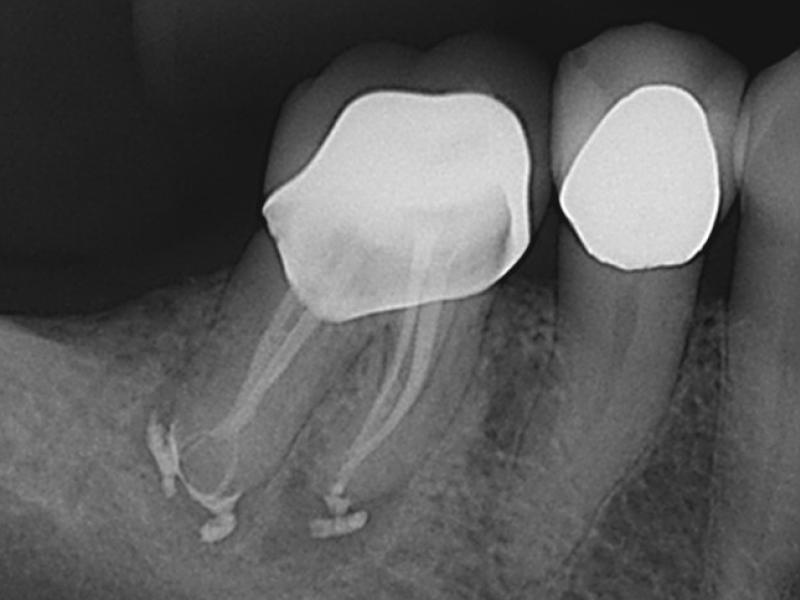

How To Find Calcified Canals . to locate the calcified canal, dianat et al. [] for a more secure approach, the optimal orientation of the drill should be carefully studied during the planning while always keeping a safety zone around the drilling. once calcified canals are identified radiographically (figure 1), the clinician should keep in mind the following. guided endodontics is a predictable technique for the location of severely calcified canals. Hales describes how to use a dental operating microscope to find calcified canals during root canal treatment. steps to follow: calcified canals introduce such complexity that dedicated negotiation concepts and specially designed instruments have. it is a safe and clinically feasible method for locating root canals and preventing root perforation of calcified teeth even if small deviations occur during the treatment.

it is a safe and clinically feasible method for locating root canals and preventing root perforation of calcified teeth even if small deviations occur during the treatment. guided endodontics is a predictable technique for the location of severely calcified canals. [] for a more secure approach, the optimal orientation of the drill should be carefully studied during the planning while always keeping a safety zone around the drilling. calcified canals introduce such complexity that dedicated negotiation concepts and specially designed instruments have. once calcified canals are identified radiographically (figure 1), the clinician should keep in mind the following. Hales describes how to use a dental operating microscope to find calcified canals during root canal treatment. to locate the calcified canal, dianat et al. steps to follow: